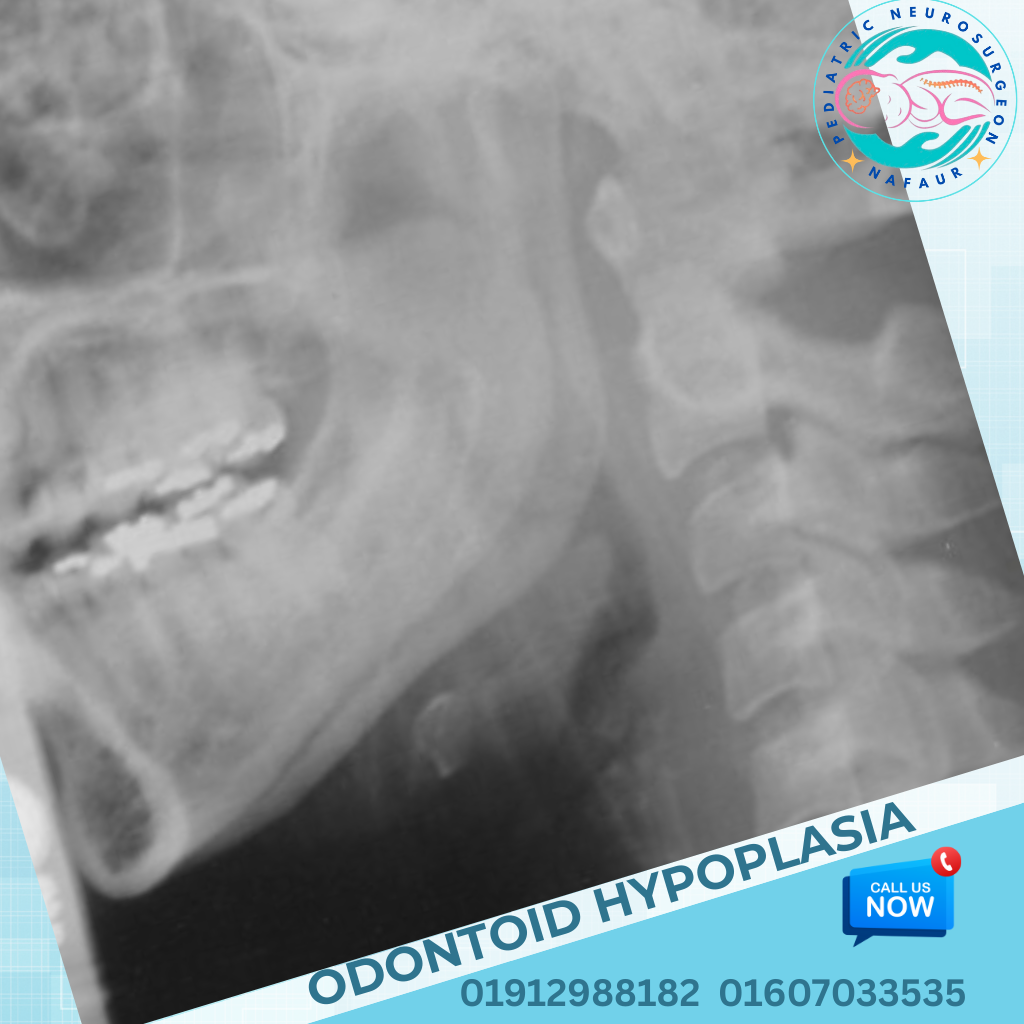

Odontoid Hypoplasia or Absence β Underdevelopment of the dens (peg-like structure of C2)

X-ray (Dynamic cervical spine views) β Shows instability

CT Scan with 3D reconstruction β For bony anomalies